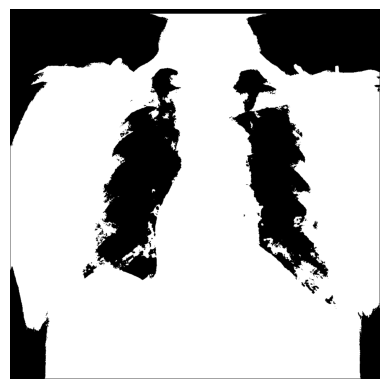

使用 np.where() 对 X 射线图像应用掩码

为了仅筛选出 X 射线图像中的特定像素以帮助检测特定特征,可以使用 NumPy 的 np.where(condition: array_like (bool), x:array_like, y: ndarray) 应用掩码,当条件为 True 时返回 x,否则返回 y。

识别感兴趣的区域 - 图像中的某些像素集合 - 可以很有用,掩码是与原始图像形状相同的布尔数组。

正如像素强度分布所示,有许多低(约在 0 到 20 之间)和非常高(约在 200 到 240 之间)的像素值。

3. 您可以使用 NumPy 的 np.where() 创建不同的条件掩码 - 例如,让我们只有那些像素超过某个阈值的图像值:

# 阈值为“大于 150”

# 如果为真,则返回原始图像,否则返回 `0`

xray_image_mask_noisy = np.where(xray_image > 150, xray_image, 0)

plt.imshow(xray_image_mask_noisy, cmap="gray")

plt.axis("off")

plt.show()

# 阈值为“大于 150”

# 如果为真,则返回 `1`,否则返回 `0`

xray_image_mask_less_noisy = np.where(xray_image > 150, 1, 0)

plt.imshow(xray_image_mask_less_noisy, cmap="gray")

plt.axis("off")

plt.show()